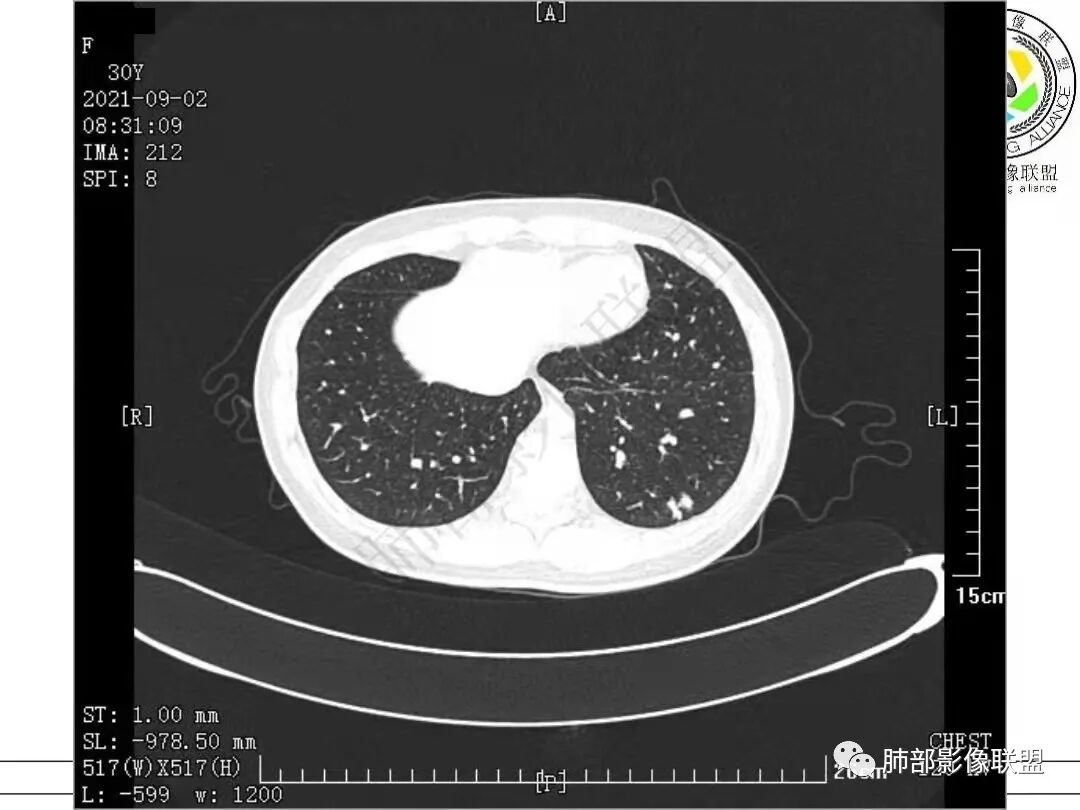

1.病例一:68岁男性,体检发现肺结节,肿瘤标志物CA199、CA50、CEA升高,其中CEA升高显著,超过正常范围的5倍以上。右肺下叶胸膜下结节影,整体较膨隆,部分层面可见锯齿状边缘,边界清晰,周围可见细毛细影,可见血管集束征、胸膜牵拉。密度不均,可见磨玻璃密度区及空泡征,胸膜下脂肪间隙显示不清。增强后显示轻、中度强化。